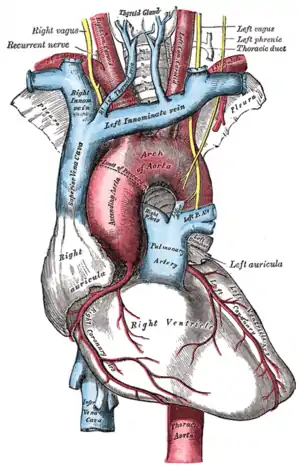

| The (right) superior vena cava (on left) and the left brachiocephalic vein (here labeled as left innominate vein). The left superior vena cava is not shown in this image. | |